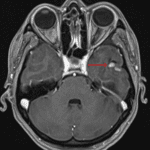

CT

- Ill-defined mixed hypoattenuating and hyperattenuating lesion in the inferior left temporal lobe

MRI

- Mixed cystic and solid mass in the inferior left temporal lobe measuring 1.6 x 1.5 x 1.3 cm with mild surrounding vasogenic edema

- The solid components diffusely enhance

- No corresponding restricted diffusion

- No substantial mass effect

Ganglioglioma